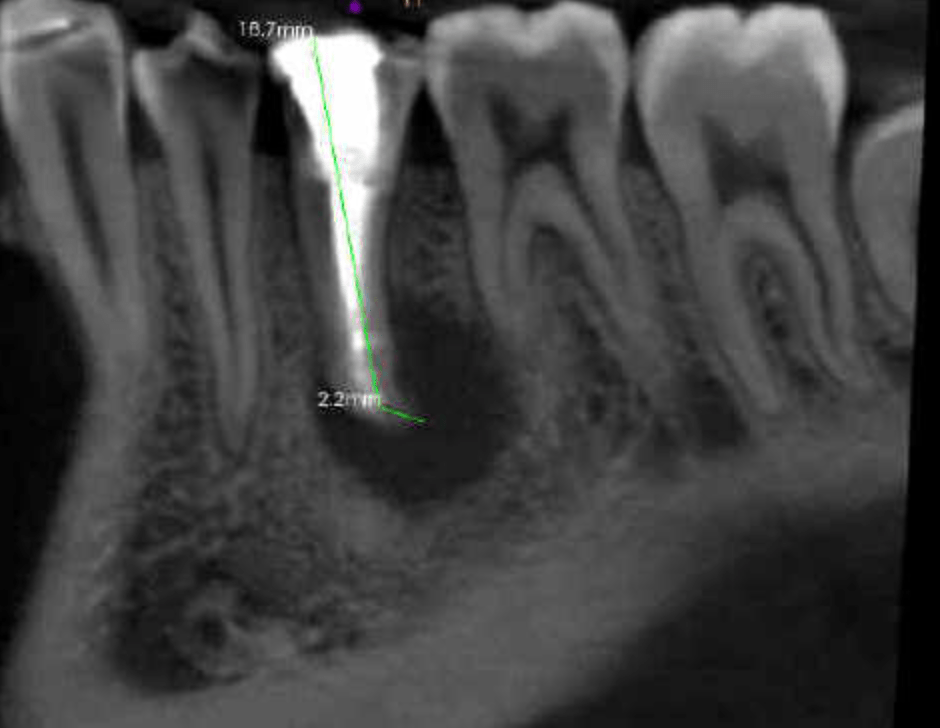

Retratamiento Primer Molar Superior